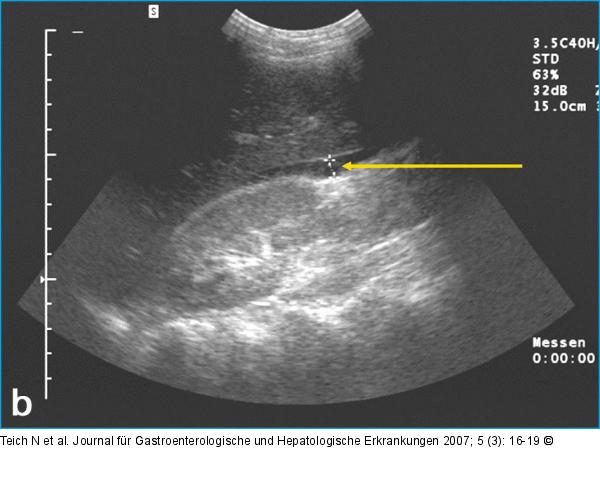

Abbildung 3b: Aszites Aszites im Spatium hepatorenale (Pfeil). |